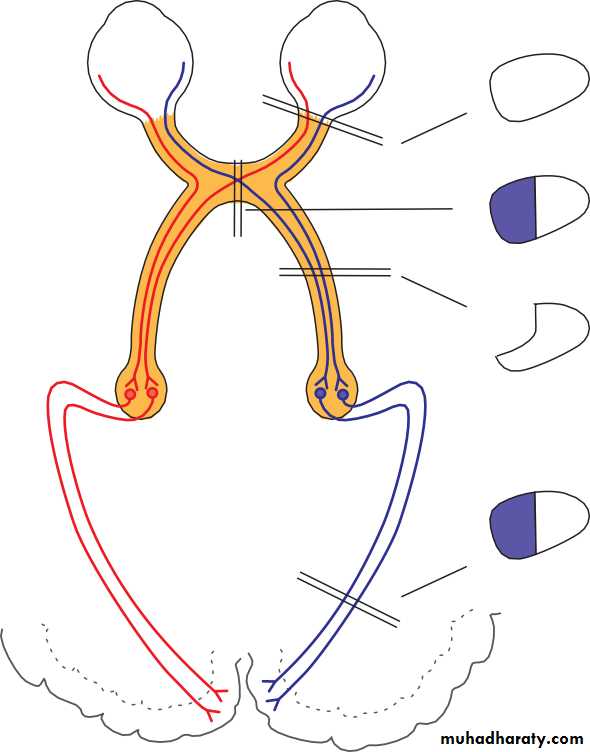

• The size of the pupils (miosis, constricted; mydriasis, dilated) and their response to light and accommodation gives important information about:

• the function of the afferent pathway controlling the pupils (the optic nerve and tract);

• the function of the efferent pathway.

• Examination of the pupils begins with an assessment of the size of the pupils in a uniform light. If there is asymmetry (anisocoria) it must be decided whether the small or large pupil is abnormal. A pathologically small pupil (after damage to the sympathetic nervous system) will be more apparent in dim illumination, since dilation of the normal pupil will be greater. A pathologically large pupil (seen in disease of the parasympathetic nervous system) will be more apparent in the light.

• In a patient in whom the pupil sizes are equal, the next step is to look for a defect in optic nerve function, using the ‘swinging flashlight test’. This is a sensitive index of an afferent conduction defect. The patient is seated in a dimly illuminated room and views a distant object. A torch is directed at each eye in turn while the pupils are observed. A unilateral defect in optic nerve conduction is demonstrated as a relative afferent pupil defect (RAPD) (see Fig. 2.4).

• Fig. 2.4 The relative afferent pupillary defect. The left optic nerve is damaged.

• (a) A light shone in the right eye causes both pupils to constrict. (b) When the light is moved to the left eye both pupils dilate because of the lack of afferent drive to the light reflex; a left relative afferent pupillary defect is present. Opacity of the ocular media (e.g. a dense cataract), or damage to the visual pathway beyond the lateral geniculate body will not cause a relative afferent pupillary defect.• Anatomical examination of the eye